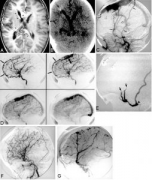

硬脑膜 脑动静脉畸形 (AVM)被认为占动静脉分流的全部颅内血管畸形的约10%至15%。尽管大多数硬膜外AVM发生在成人中,但在新生儿,婴儿和儿童中有这些病变的零星报道。目前的观...

出国看病: 脑动静脉畸形 出血的风险到底有多大?脑动静脉畸形(AVM)的总体年出血率约2-4%,但这不适用于全部的脑动静脉畸形(AVM),部分脑动静脉畸形(AVM)潜在的解剖和血流动...

脑动静脉畸形 (AVM)由异常连接的动脉和静脉组成,血管包括动脉和静脉两种主要类型。动脉将富含氧气的血液从心脏带到身体的各个部位。随着动脉深入组织,它们分支到较细的血管...